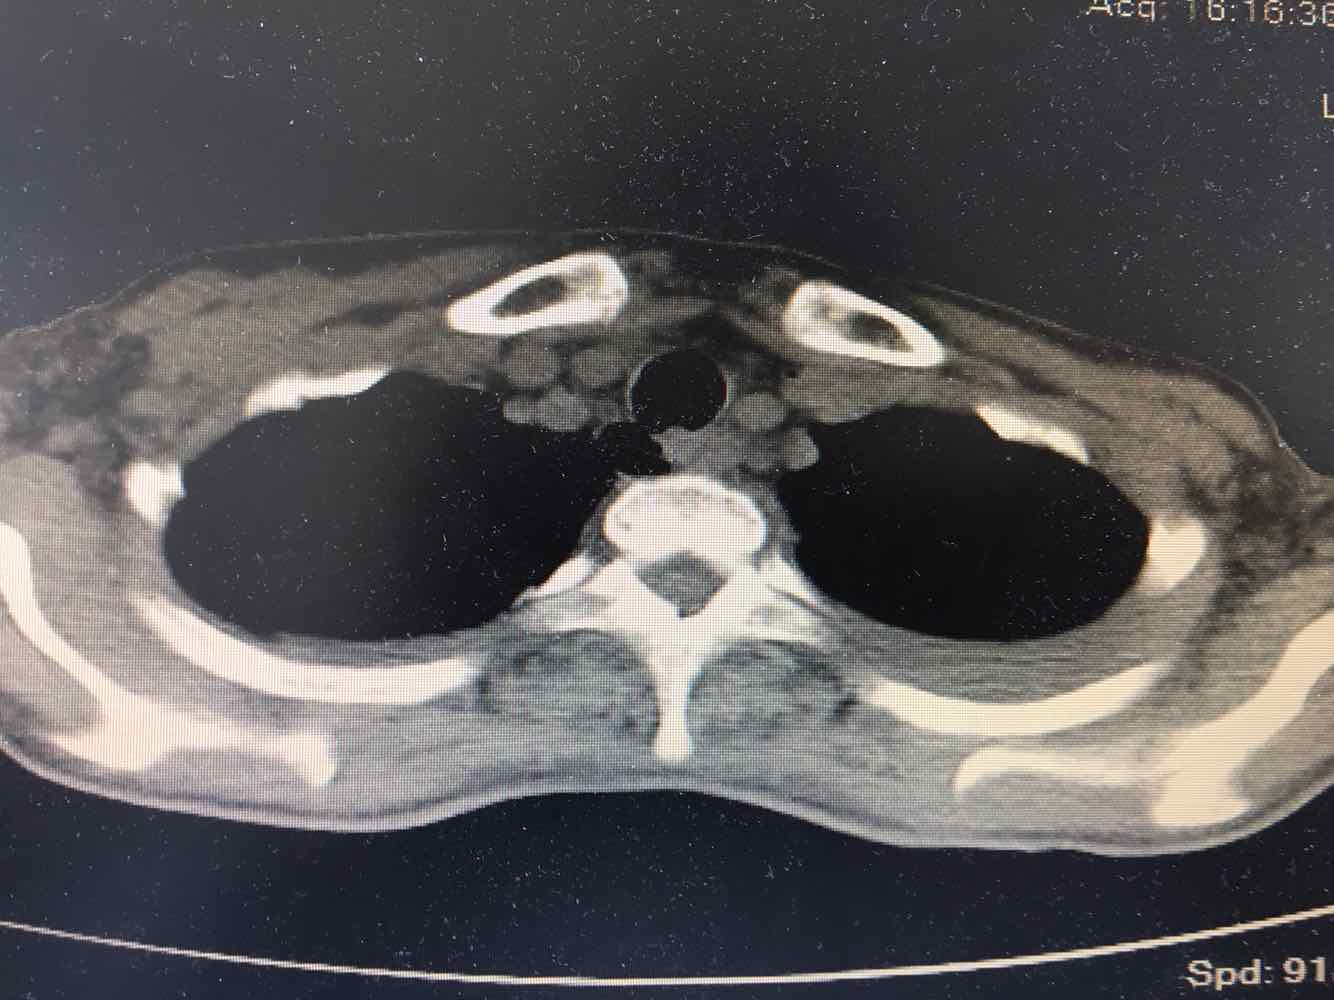

女,51岁,支气管扩张病史多年。慢性咳嗽咳痰喘息30年,加重1个月,无发热,气短为主,痰液不多,上腹不适,少尿。双肺干湿罗音。